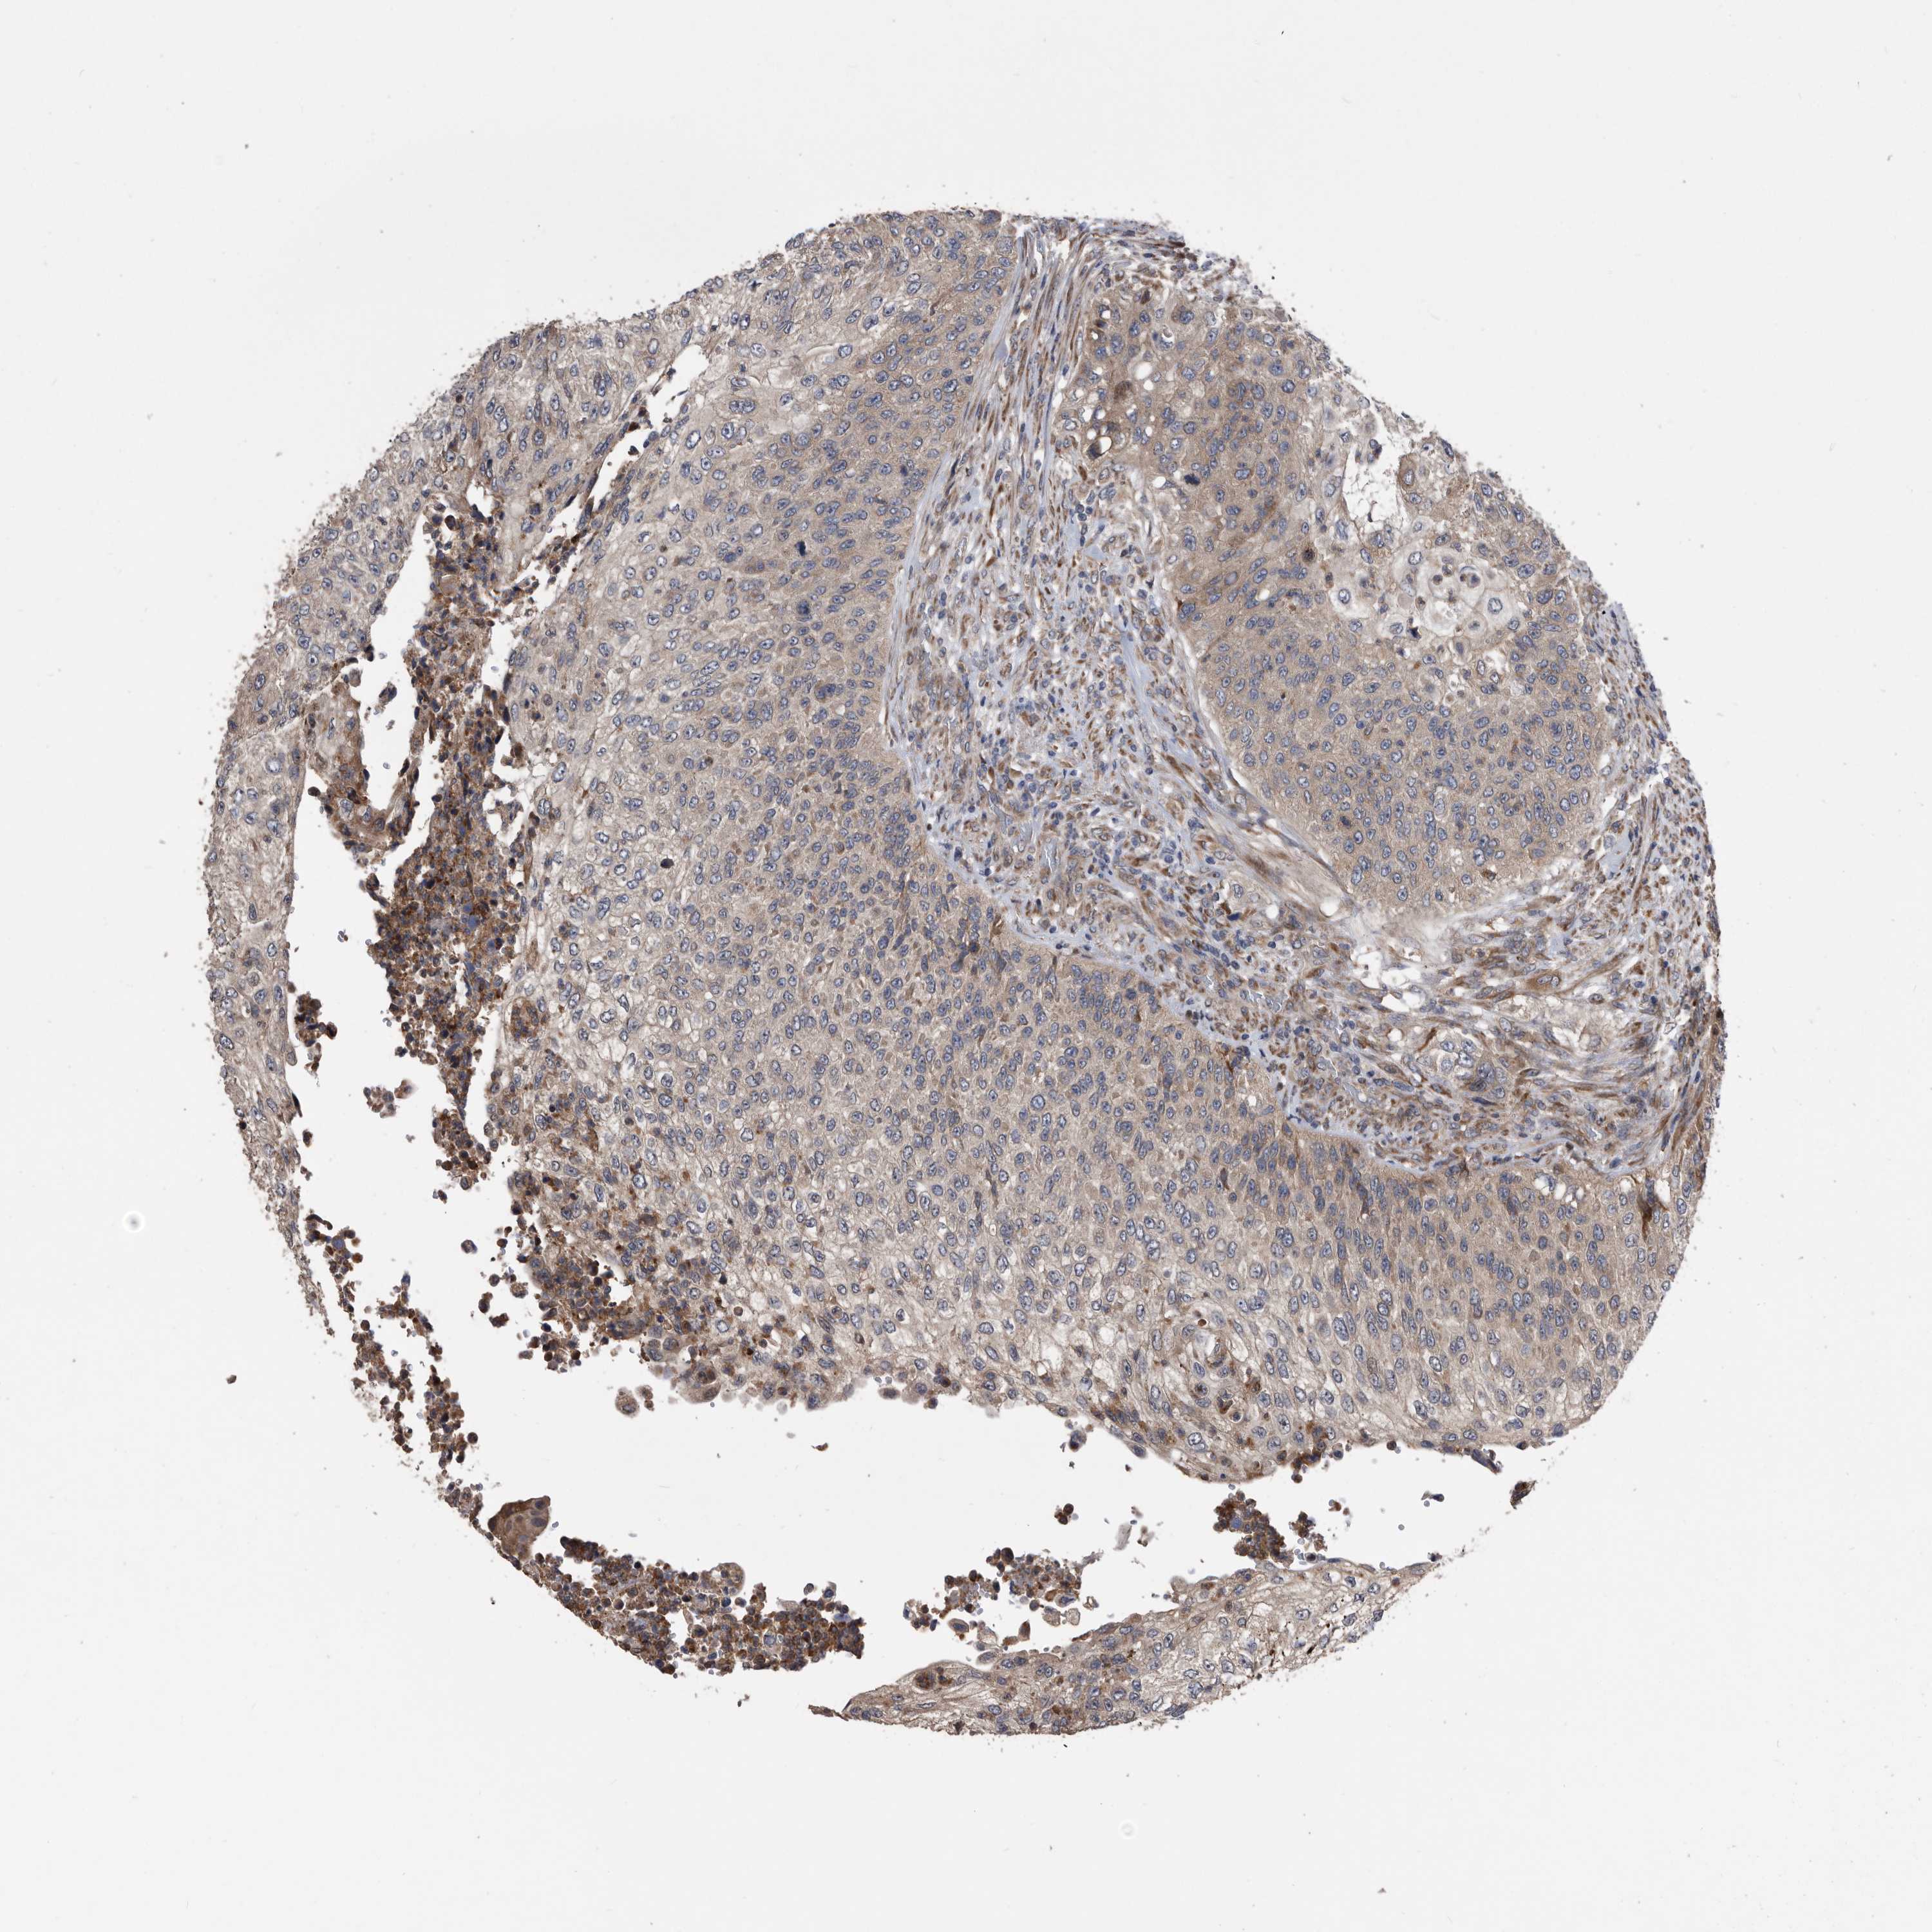

UROTHELIAL CANCER - Protein expressioni

A mouse-over function shows sample information and annotation data. Click on an image to view it in a full screen mode. Samples can be filtered based on level of antibody staining by selecting one or several of the following categories: high, medium, low and not detected. The assay and annotation is described here.

Note that samples used for immunohistochemistry by the Human Protein Atlas do not correspond to samples in the TCGA dataset.

Antibody stainingi

Antibody staining in the annotated cell types in the current human tissue is reported as not detected, low, medium, or high, based on conventional immunohistochemistry profiling in selected tissues. This score is based on the combination of the staining intensity and fraction of stained cells.

Each image is clickable and will lead to virtual microscopy that enables deeper exploration of all samples and also displays staining intensity scores, fraction scores and subcellular localization as well as patient and tissue information for each sample.

Antibody HPA005974

Staining

High

Medium

Low

Not detected

Intensity

Strong

Moderate

Weak

Negative

Quantity

>75%

75%-25%

<25%

None

Location

Nuclear

Cytoplasmic/membranous

Cytoplasmic/membranous,nuclear

Urothelial carcinoma, Low grade

Urothelial carcinoma, High grade